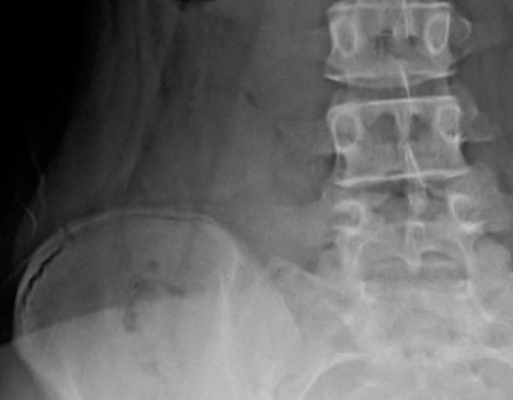

Wie die Risser Score Skoliose Behandlung: Ein umfassender Überblick

Learn how the Risser Score influences scoliosis treatment. This comprehensive guide provides valuable insights for [...]